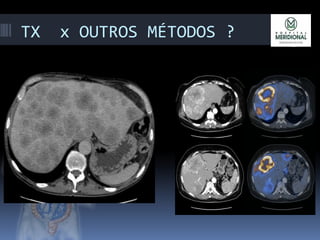

TX x OUTROS MÉTODOS ?

TX x OUTROSMÉTODOS ?